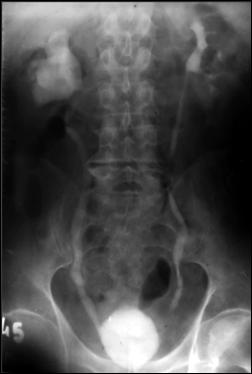

1. Diagnosticul diferential cu litiaza vezicala radiotransparenta

Ecografia vezicii urinare evidentiaza imagine hiperecogena, cu con de umbra posterioara (calcul)

Figura 54. Imagine radiotransparenta (2,5/1,8 cm, vizibila pe cistografie) |